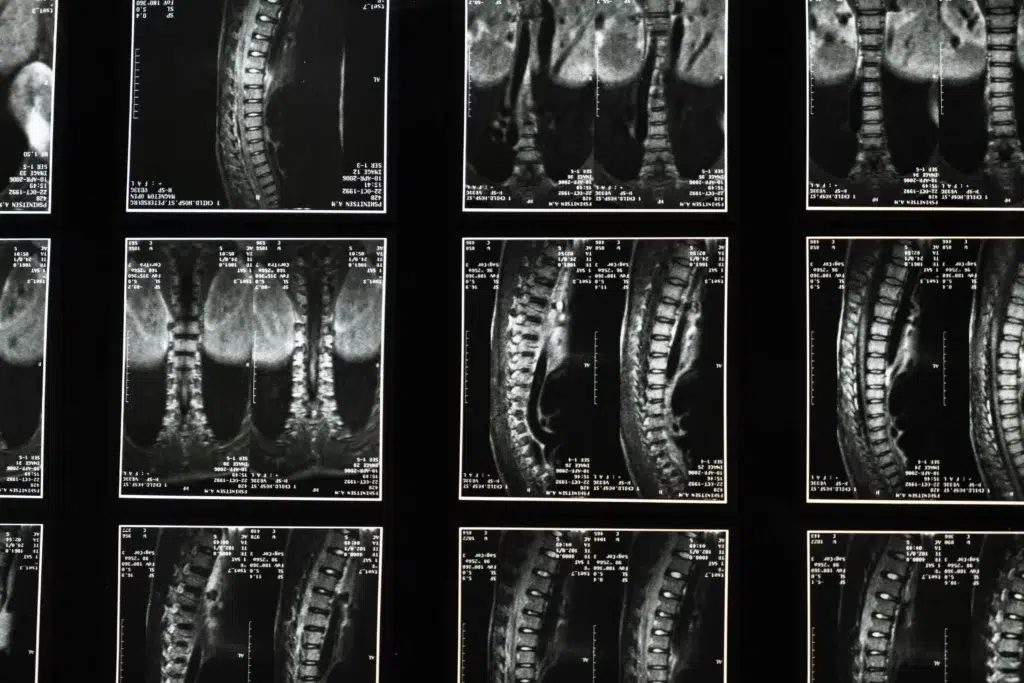

IRM (Imagerie par Résonance Médicale)

Identifie l’étendue et la localisation de l’œdème avec une grande précision.

Une IRM est souvent indispensable pour confirmer le diagnostic d’un œdème osseux au niveau de la colonne lombaire. Découvrez davantage sur les tests et diagnostics de douleurs osseuses en consultant notre article sur l’œdème osseux du plateau tibial ou celui de l’œdème osseux du pied.